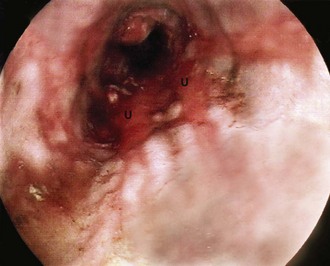

On gastroscopy, reflux oesophagitis is characterised by mucosal reddening and, in more severe cases, by typical linear superficial ulceration (see Fig. 21.4). Peptic strictures occur in the distal oesophagus and are usually located just above the oesophago-gastric junction, which itself often lies above the diaphragm because of inflammatory shortening of the oesophagus. The normal oesophago-gastric junction is about 40 cm from the incisor teeth when seen on endoscopy. Specialised intestinal metaplasia, dysplasia and carcinoma must be excluded by biopsies because the visual appearances may not be characteristic. Occasionally, a deep chronic ulcer occurs in the lower oesophagus; this looks and behaves like an often linear gastric or duodenal ulcer. When squamous oesophageal epithelium is repeatedly damaged by reflux, it may be replaced by metaplastic columnar epithelium. This is known as Barrett's oesophagus and there is strong evidence that it predisposes to malignant change. If found, it should be biopsied to exclude dysplasia. When dysplasia is severe, there is about a 1% annual risk of malignant change and endoscopic resection or surgery is necessary. Standard protocols are usually employed for surveillance of Barrett's oesophagus with repeated endoscopy every 2–3 years.

Fig. 21.5 Peptic ulcers

(a) Lesser curve benign gastric ulcer as seen through a gastroscope. At the original examination, the ulcer could be viewed from several directions and biopsies taken of the edge to exclude malignancy. (b) Photograph taken at emergency laparotomy for bleeding duodenal ulcer. The pylorus has been opened longitudinally and a deep chronic posterior ulcer crater is identified (arrowed). Thrombus T overlying an eroded artery is visible. A bleeding artery in the ulcer crater was under-run with sutures to arrest the haemorrhage